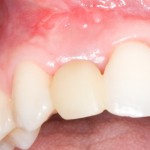

В таких случаях пациенту нередко предлагается какая-то съемная протетическая конструкция (в народе называемая «бабочкой» или «жучком»), задача которой — замаскировать отсутствие зуба до его восстановления с помощью импланта:

И, я должен заметить, что с маскировкой такой простейший протез отлично справляется: